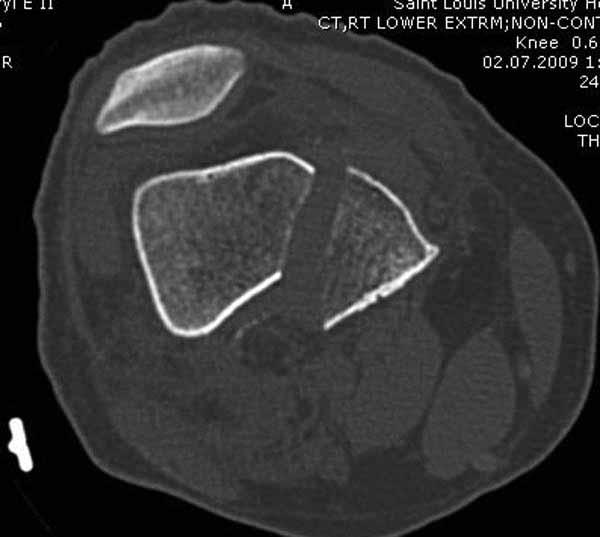

Представленный снимок не дает полную информацию. Там вроде простой перелом, но на самом деле, кроме смещенного (латерального, возможно медиального?) мыщелка на второй проекции имеется медиальный короткий дистальный фрагмент в флексии. Надо было сделать прямой снимок с захватом малоберцовой, который ориентировал бы стороны. Без КТ обычный снимок в дистракции поможет разобраться в топографии фрагментов.

Кстати, из вашего снимка, если отмечены вашим рентгенологом правильно, тогда получается снимок левого колена, и, соответственно, длинный переходящий в диафиз мыщелковый фрагмент находится медиально. Если так, тогда меняется сценарий фиксации!!!

И не обратите, коллега, пока не сделаете четкие анфасные снимки (лучше с дистракцией) где будет четко визуализироваться малоберцовая кость. Думается, что и КТ здесь будет уместно, дабы не пропустить возможное флексионное повреждение (перелом Hoffa).

А теперь по поводу лечения перелома. Среди всех чрез/меж-мыщелковых переломов в 38% сопровождются переломом в корональной плоскости, т.е перелом Hoffa. Nork et al, J Orthop Trauma, 87:564, 2005.

У больных как в этом случае, с вовлечением двух мыщелков правильно, что сделали вытяжение до операции. Здесь имеется флексионный компонент на другой стороне, и я бы рекомендовал операцию делать из двух доступов. Сперва фиксировать медиальную колонну custom made пластиной, обычно 1/3 тубулярной пластиной в 4.5 мм, потому что пока производители опаздывают с медиальной пластиной.

Здесь пример медиальной пластины и латеральный комбинированный метод (у второго больного старый перелом тибиал плато, леченный где то и когда то)